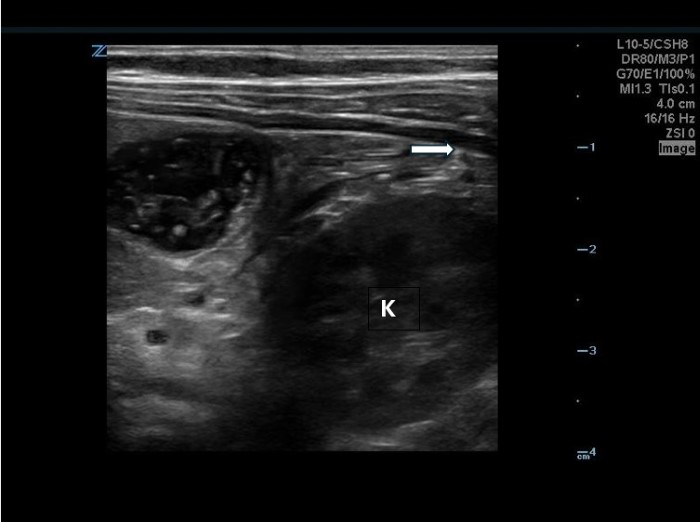

The linear probe is placed in the RLQ in the transverse position with indicator to the patient’s right. Identify the psoas muscle and iliac vessels lying medial. Once these structures are visualized, slide lateral and look superficially to identify the cecum. (Figures 1a,1b 1) Use graded compression-progressive increase and decrease of pressure to move any gas out of view. Keeping the lateral edge of the abdominal cavity in view (Figure 2), the ultrasound probe should slide cranial in traverse plane, visualizing the ascending colon until the hepatic flexure.  In this location, the colon turns just medial to the liver with the kidney deep in the view. (Figure 3) This is the most common location to identify ileocolic intussusception. If no tissue mass is identified, the probe should be turned to the sagittal plane with indicator toward the head (to keep the colon visualized in the transverse view) and moved across the transverse colon continuing to use graded compression to look for a tissue mass consistent with intussusception. Once at the splenic flexure (Figure 4), the probe should be transitioned back to the transverse orientation to interrogate the descending colon.

10-2024 Article7-3.jpgFigure 3. Hepatic flexure view in a patient with intussusception. Oblique abdominal muscles, liver, kidney visible. Intussusception will be medial to the liver and superficial to the kidney.